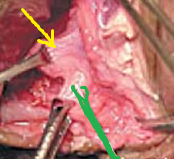

Πράσινο βέλος – εστιακή εξέλκωση κολικού βλεννογόνου. Κίτρινο βέλος – οίδημα και λεμφοκυτταρική διήθηση υποβλεννογόνιου χιτώνα (Ευγενική παραχώρηση Dr. V. Penopoulos)